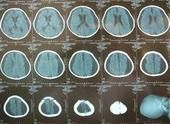

4. 影像學檢查: 頭顱CT可正常,也可見一側或雙側顳葉、海馬及邊緣系統局灶性低密度區,若其中出現點狀高密度提示有出血性壞死,更支持診斷。嚴重者可有腦室受壓、中線移位等占位效應。在早期MRI T2加權像可見到顳葉中、下部,向上延伸島葉及額葉底面有周邊清晰的高密度區。MRI優於CT,尤其可發現早期病灶。

單純皰疹病毒性腦炎(5)頭顱CT或MRI發現顳葉局灶性出血性腦軟化灶;